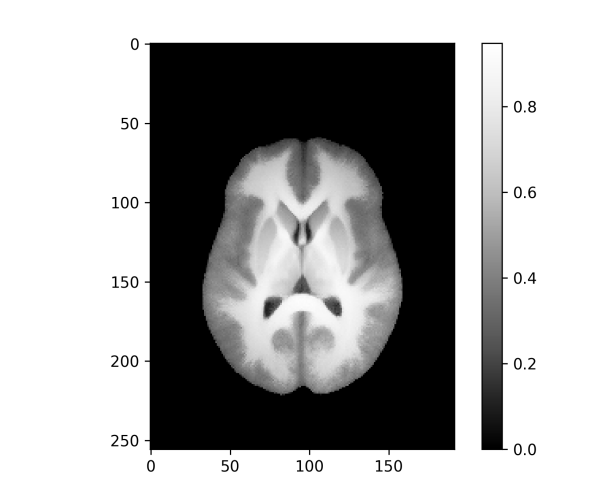

As already mentioned, for real images given on a discrete domain that approximates the underlying continuum , the minimization is performed numerically with a discretized version of the functional . After minimizing the optimal parameters and the template are obtained. The registered images are now aligned with the template. Figure 2 shows an example of a registered sample image for the 3d example dataset from Subsection IV-B together with template images for the - and -norm for affine transformations.

An important application of image registration is the preprocessing of 3d MRI brain images. Here a collection of brain images (possibly from different subjects) are registered with a template, here also called an atlas, which enables more direct comparisons between different brains despite differences in the respective brain geometry before registration. The dataset used here for demonstration purposes is the Neurofeedback Skull-stripped (NFBS) dataset [9], which contains 125 raw MRIs and their skull stripped versions. The intensities of the sample images are normalized such that the median of each image (without the background zeros) is mapped to . Additionally, we are optimizing an intensity scaling factor for each image during the registration such that the scaled template matches the registered image under the similarity metric. This minimizes the vertical variability and brings us a bit closer to the model situation of the shifted edges. The effective height for the resolution measure is chosen as .

For the skull stripped brains a template is generated for affine and rigid transformations and for - and -norm similarity measures, as shown in Figure 10. In each of the four cases the template resolution is computed with Algorithm 1 and horizontal slices of the resulting 3d images of the values are shown in Figure 11 and visualized on top of the template, as described in Subsection III-D, in Figure 12.